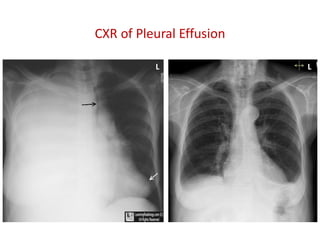

CXR of Pleural Effusion

L L